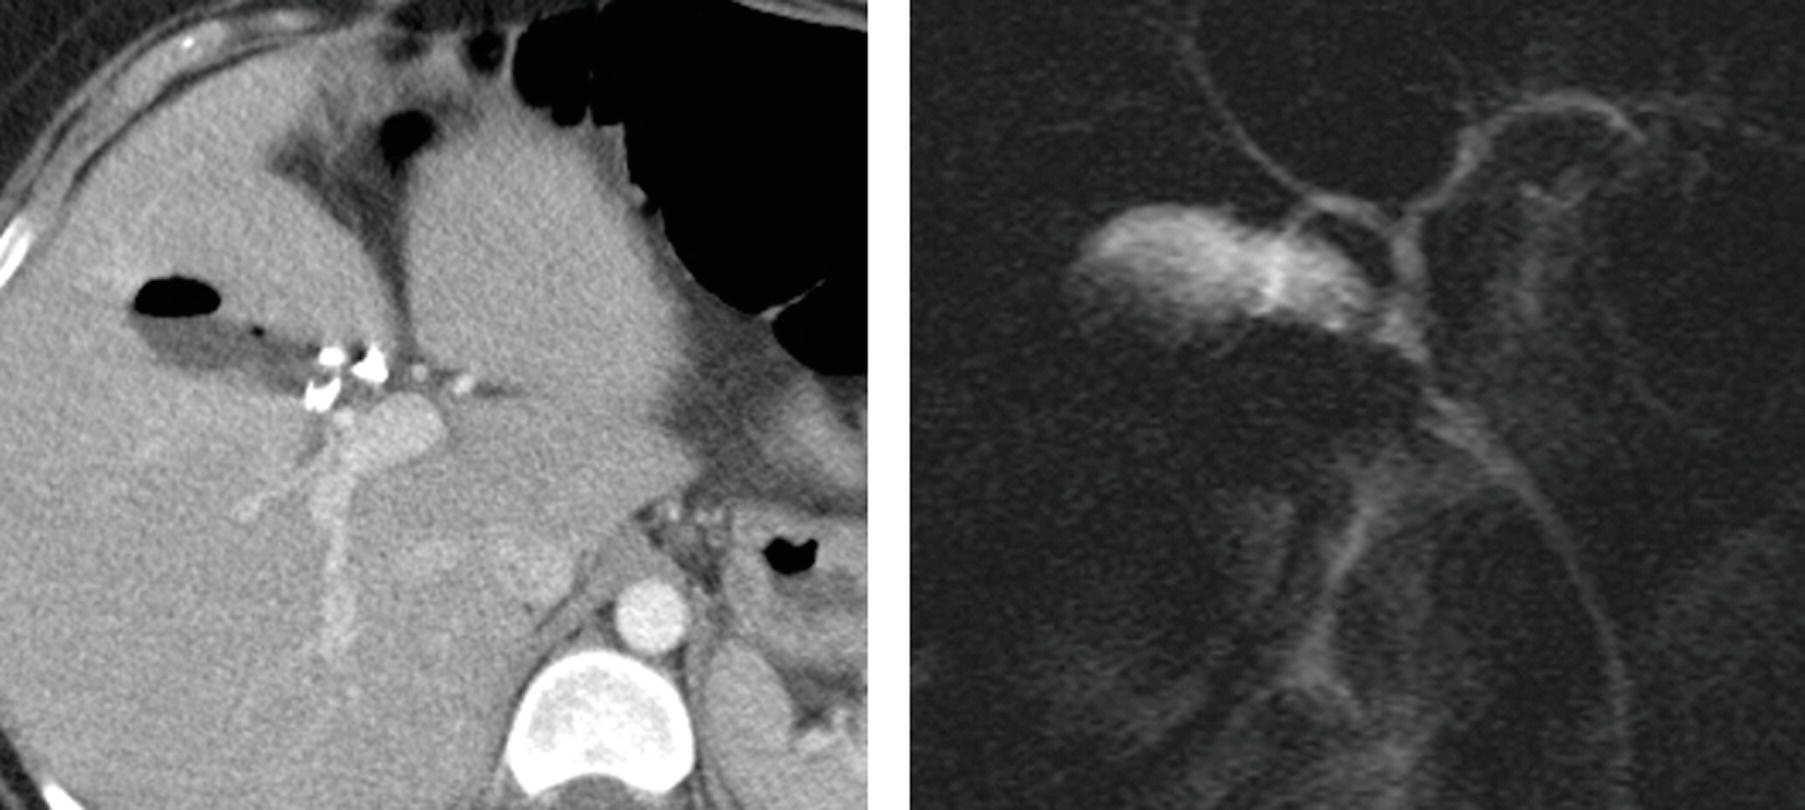

ERCP for two patients showing bile leak from the cystic duct (dotted How To Diagnose A Bile Leak The use of ercp and ptc can identify a continuing bile leak, provide exact anatomical diagnosis, and allow, at the same time, the. Diagnosing a bile duct leak. With these symptoms, workup with further labs and imaging should be performed to confirm the diagnosis of a bile leak. A multidisciplinary approach for treatment of biliary leaks with prompt referral to. How To Diagnose A Bile Leak.